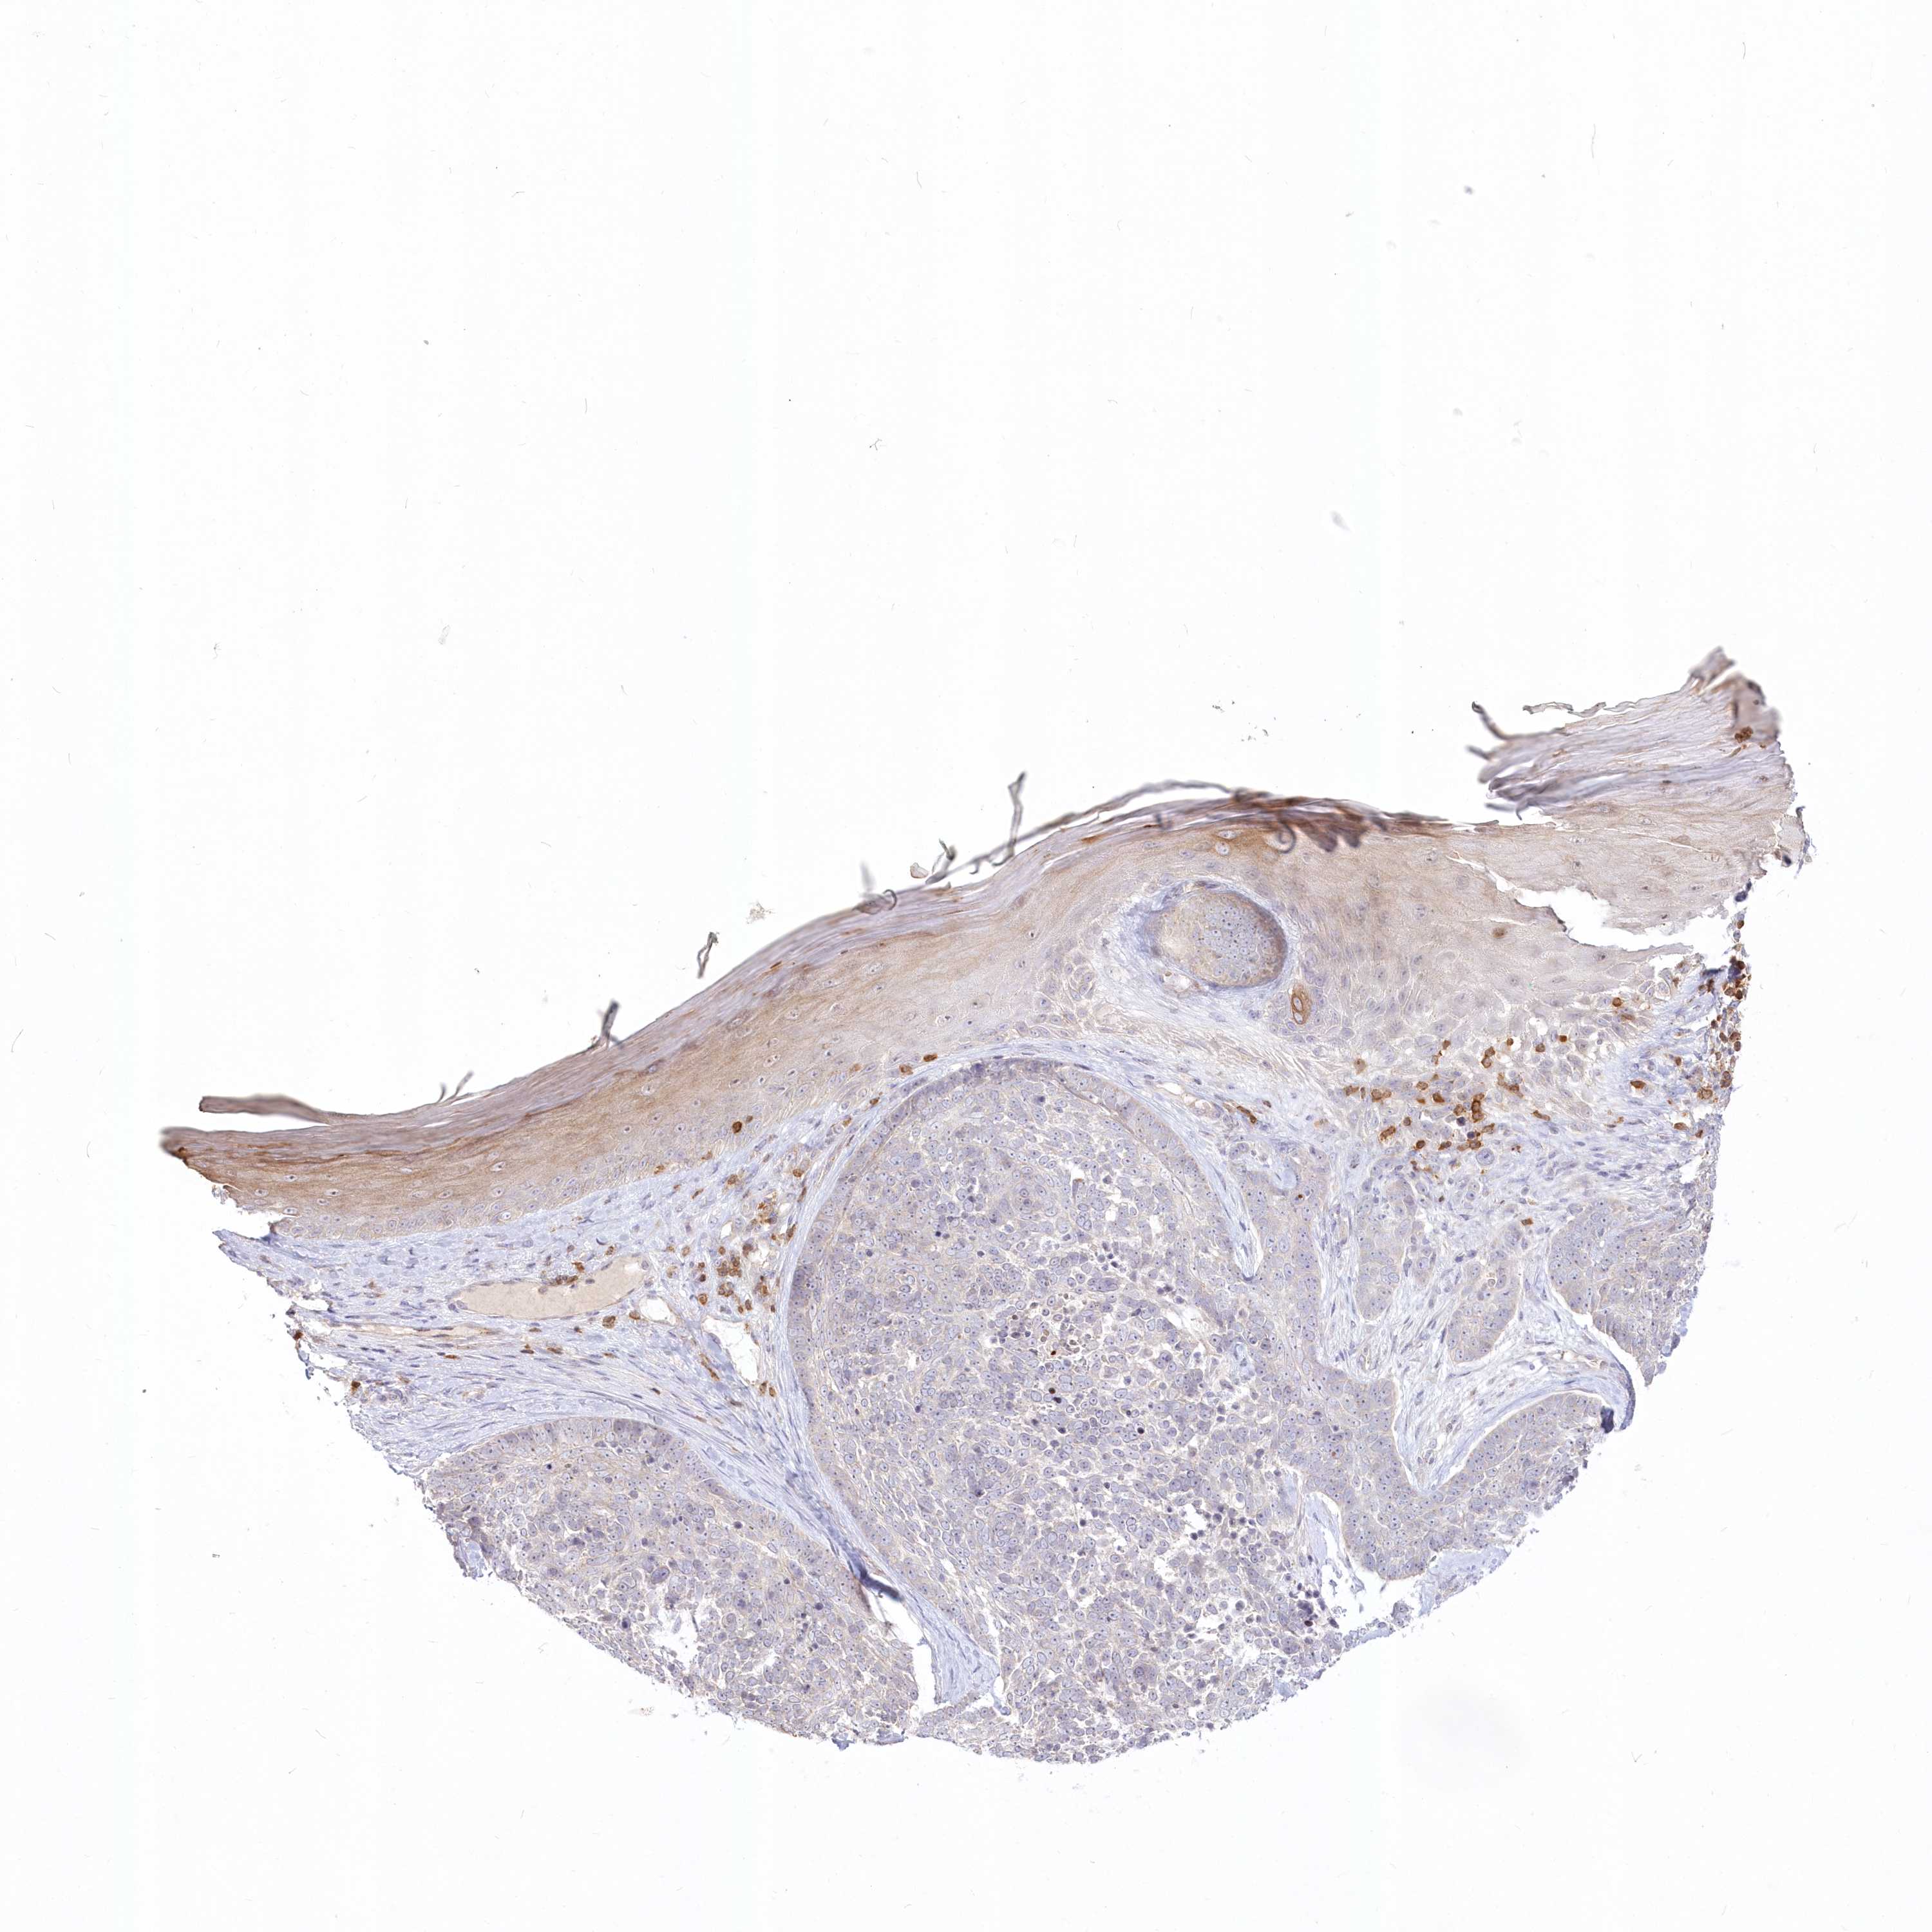

Antibody HPA034516

Squamous cell carcinoma, NOS